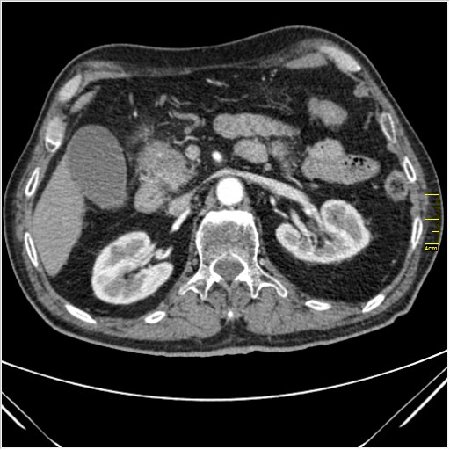

Мужчина 62 года с желтухой

Опухоль головки поджелудочной железы, расширение холедоха и панкреат. протока (Double Channel sign)

Карциномы панкреас гиподенсны на КТ с болюсом, т.к. содержать много соединительной и фиброзной ткани, в отличие от нормальной ткани железы, которая (как любая железа) хорошо васкуляризирована. Поэтому если видим в панкреас солидное гиподенсное образование - всегда настораживает на предмет рака. Второй момент: обязательная оценка взаимоотношения опухоли к ВБА и ВБВ, на предмет оценки операбельности.

pancr7.JPG

pancr7.JPG (62.38 КБ) 2898 просмотров